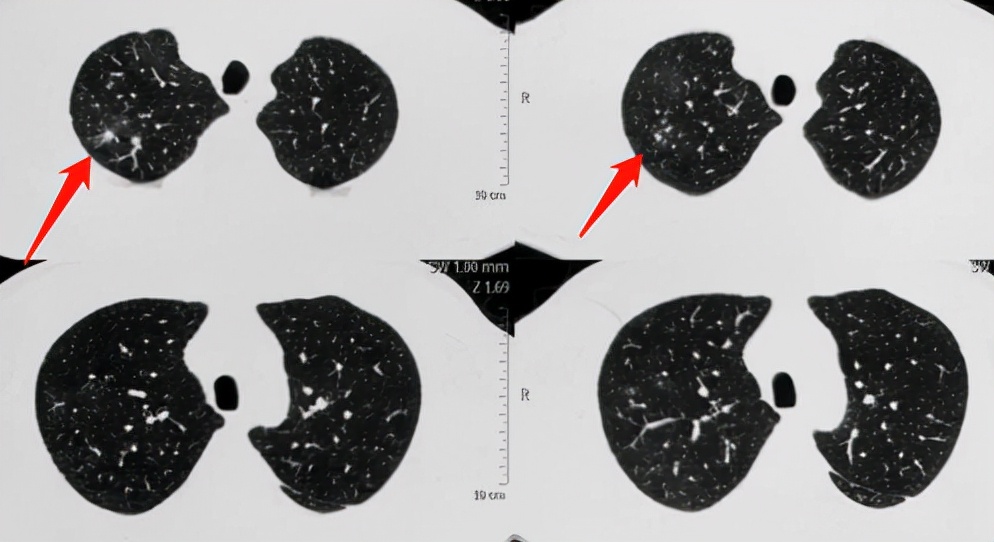

这是一位公司职员,中年男性,经常出差,单位体检时发现右肺阴影:

上肺有几个白色小结节,周围有一圈模糊的磨玻璃影,就像光晕一样(晕征)。

结果4个月后,出现咳嗽、痰中带血,回医院复查CT,发现病灶明显增大、增多了: